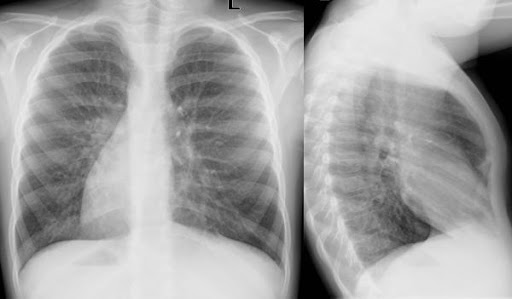

Транспозицията на органите е открита от неонатолози при рутинния преглед непосредствено след раждането на момиченцето. „Бях изненадана да чуя, че сърдечните тонове се улавят по-добре в дясно. При направената рентгенова снимка се установи разположение на органите обратно на това, което трябва да бъде“, каза д-р Зорница Василева.

Ситус инверсус обикновено не повлиява качеството на живот. В около 25% от случаите се наблюдава синдром на Картагенер, свързан с хроничен възпалителен процес в белите дробове. Бебето е насочено за последваща консултация с пулмолог.